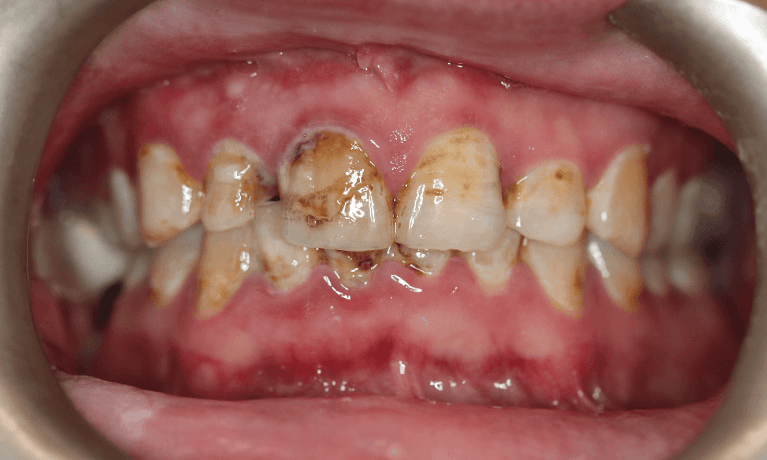

This patient presented with discolouration and uneven tooth shapes, eager to achieve a brighter, more uniform smile. Through the artistry of porcelain veneers, we were able to completely revitalise their smile.